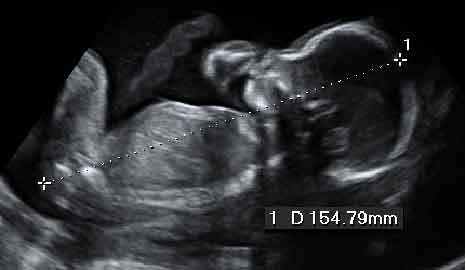

La misma imagen en 2D

Imagen de una ecografía en 2D de los genitales femeninos de un feto en la semana 20 de gestación y la misma instantánea en 4D, mucho más clara para el público en general. Aunque desde el punto de vista de los ginecólogos, la información que les ofrece es similar.

En la imagen de la izquierda se aprecian los genitales de niña en imagen 2D y a la derecha, más claramente, en 3D, se observan las piernas, los glúteos y los genitales. Para obtener la imagen en tres dimensiones, primero se ajusta la imagen en 2D de la zona de interés. Posteriormente se pasa esa imagen a 3D, lo que permite visualizar el volumen de la imagen.